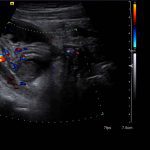

- Tubular, blind-ending structure in the right lower quadrant measuring 9 mm in diameter, which is noncompressible with mild wall thickening and mild mural hyperemia

- An abscess should not have internal blood flow, but commonly will have peripheral hyperemia